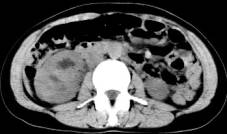

病历摘要:女性,35岁。右腰隐痛,排无痛性肉眼血尿9个月,体查右肾区轻度叩痛。行IVP及CT检查。